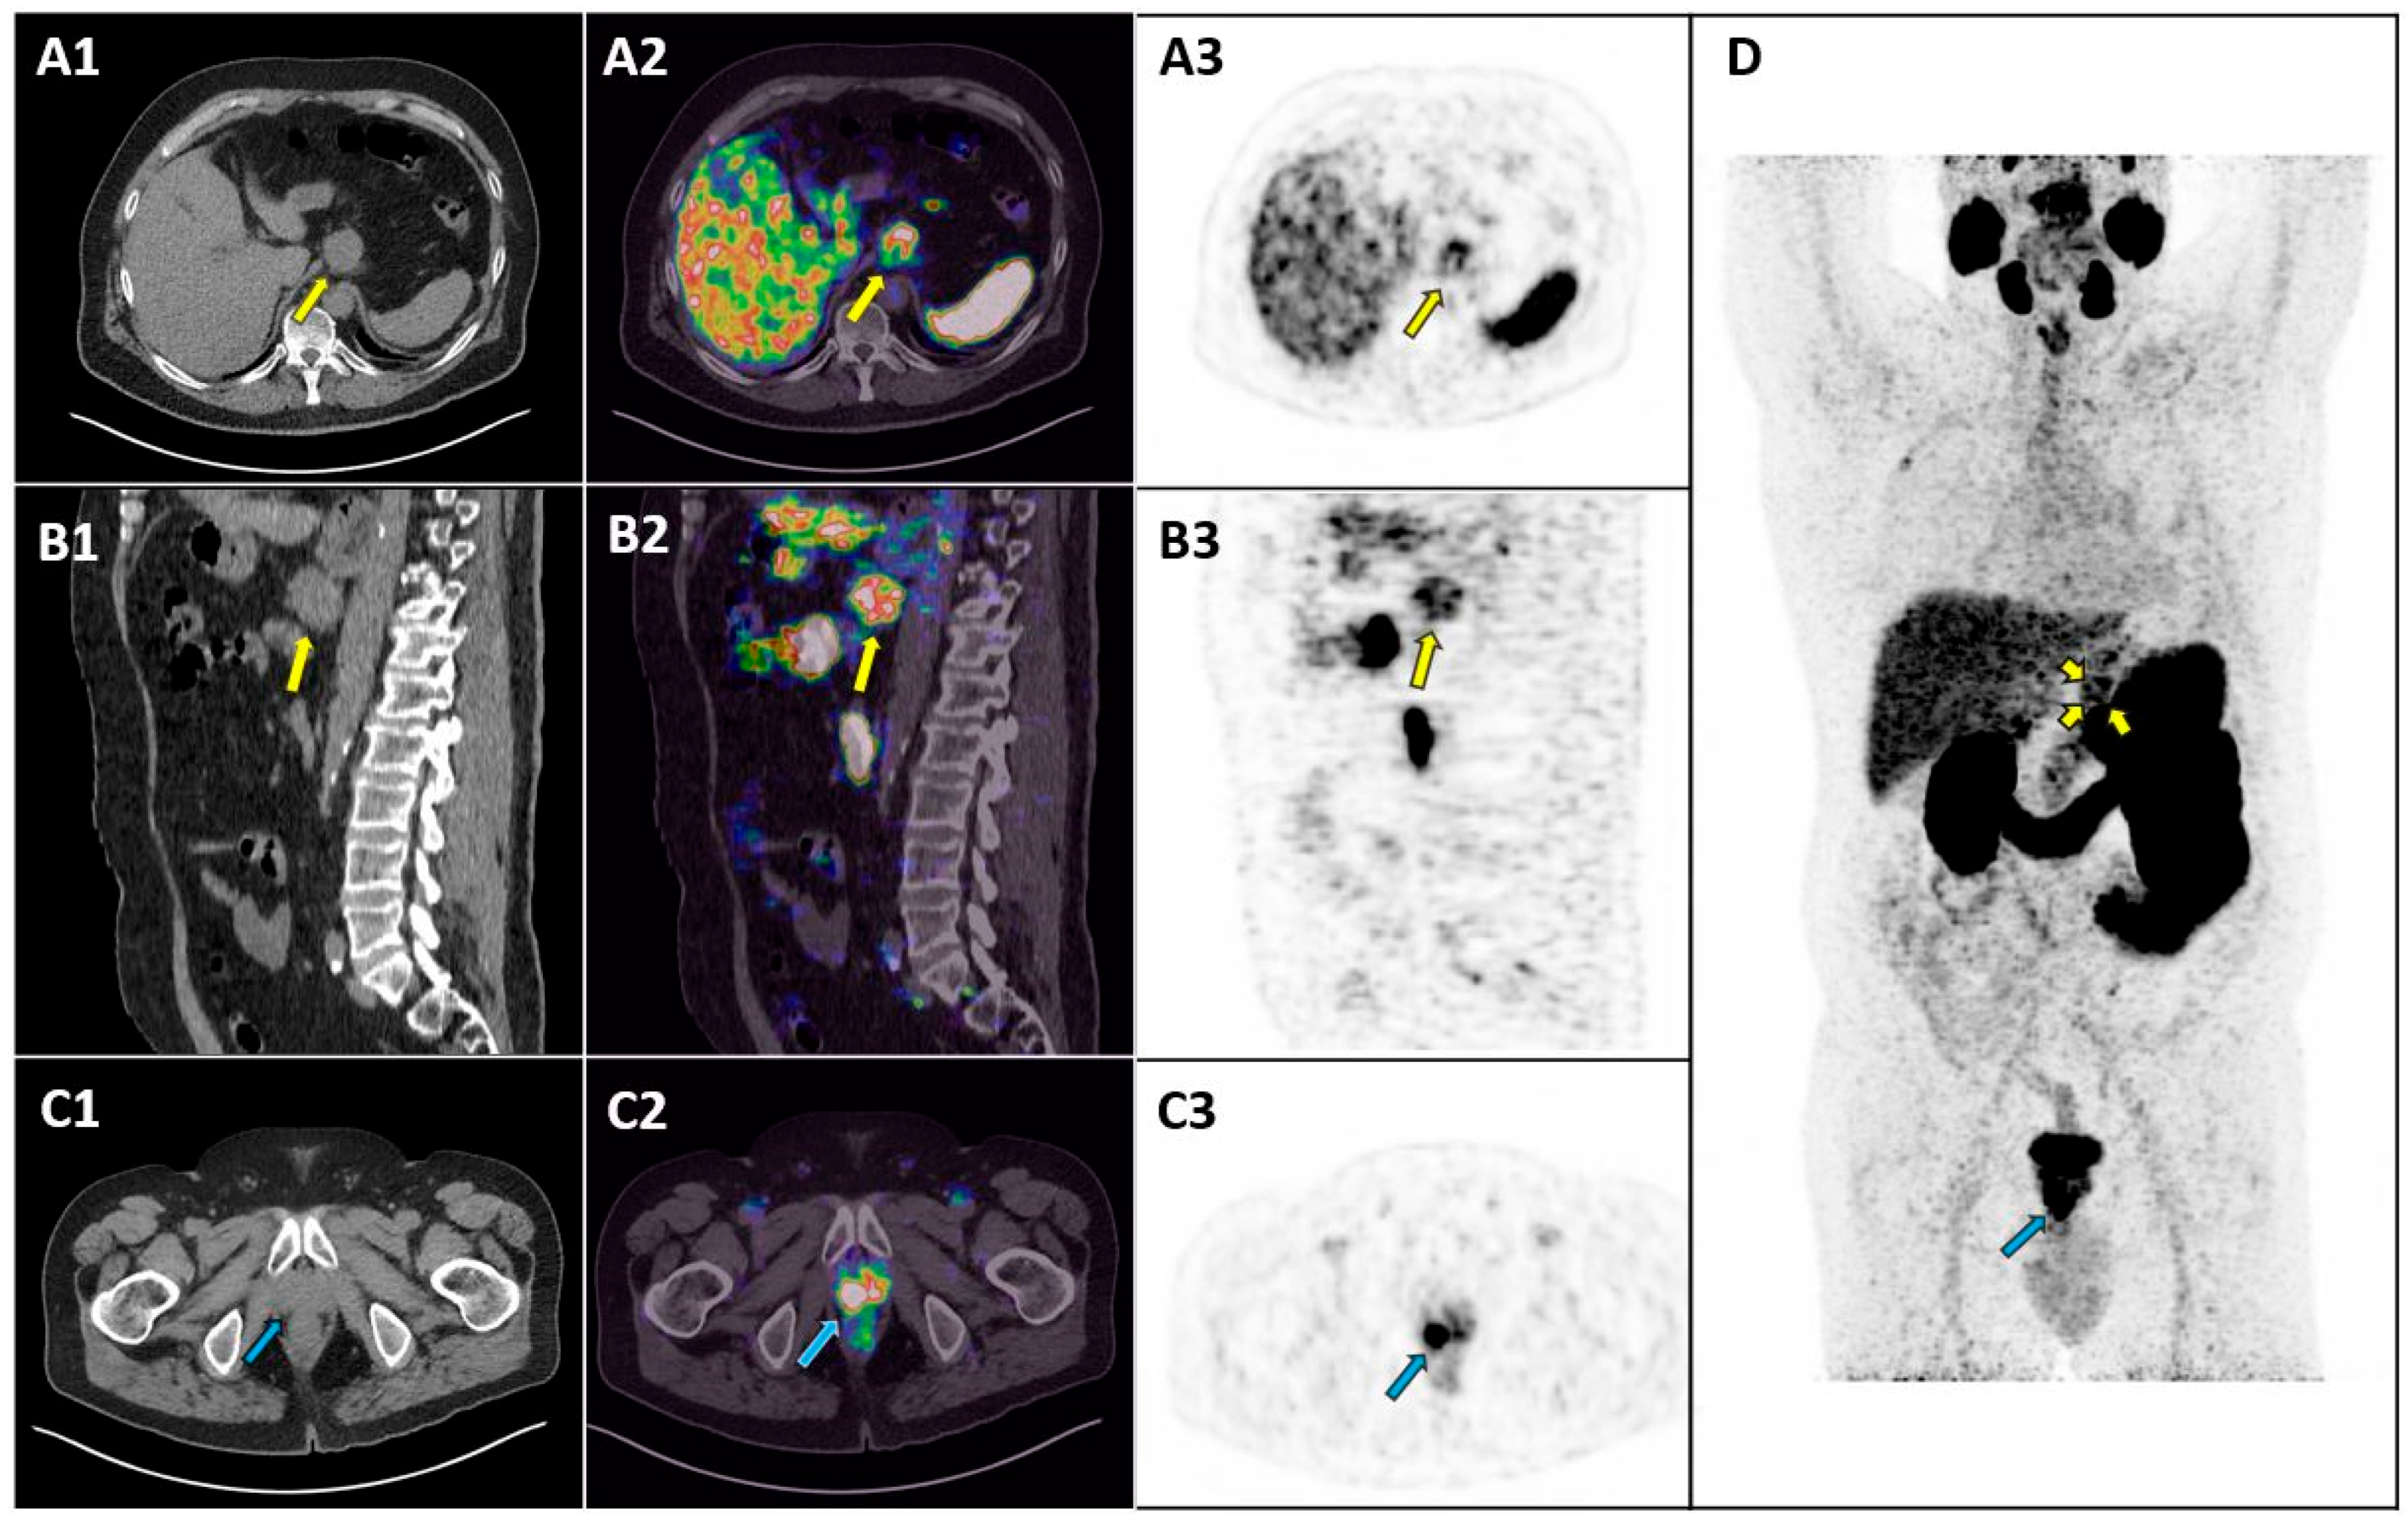

Gastric Adenocarcinoma Incidentally Detected by PET/CT with PSMA Ligands

Iacovitti, C.M.; Muoio, B.; Cuzzocrea, M.; Paone, G.; Treglia, G. Gastric Adenocarcinoma Incidentally Detected by PET/CT with PSMA Ligands. Diagnostics 2025, 15, 101. https://doi.org/10.3390/diagnostics15010101